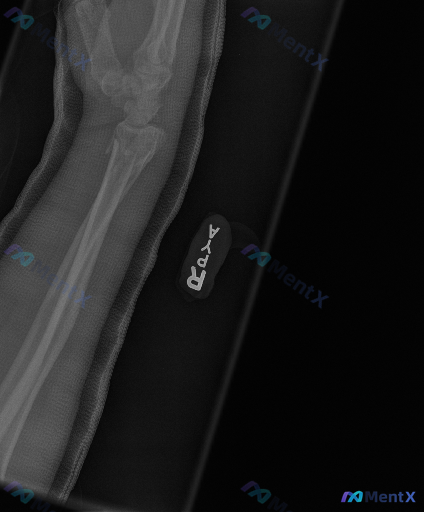

整理到一份右侧前臂及腕关节的X光片影像分析资料,给大家同步一下核心发现,一起讨论后续的评估与观察重点: 病例影像背景 - 拍摄部位:右侧前臂+腕关节 - 已有处理:影像中可见外固定装置覆盖 主要影像学异常 1. 骨骼连续性:桡骨远端可见明显骨折线,骨皮质中断,有断端移位和背侧/桡侧成角畸形,同时伴尺...